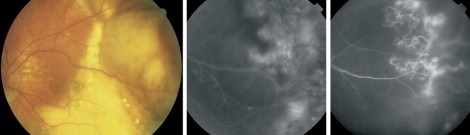

Retinal macroaneurysm[27] |

Coat's disease with telangiectasias in the temporal periphery with the presence of exudates and subretinal fluid[28] |